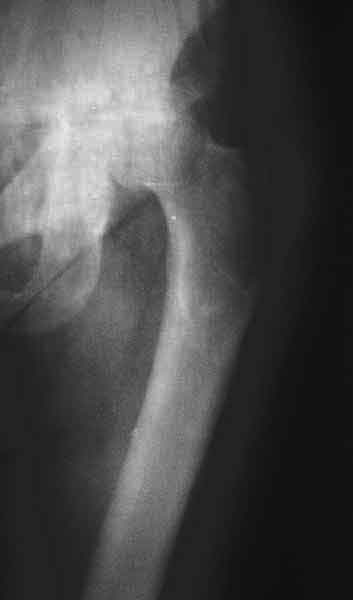

AV> опираясь на стул. На ногу не наступает. Укорочение 8 см. Иногда

А за счет чего такое укорочение? По снимку не видно соответствующего дефекта. Ну плюс приводящая контрактура - но все равно как-то уж больно много. Может, сделать снимки и таза обзорный с обоими проксимальными отделами бедра, и коенный суставов с приложенной линейкой какой?

Судя по снимку, максимум истинное укорочение около 4 см, что может быть коррегировано интраоперационно. Вопрос в другом: куда ставить ацетабулярный компонент в истинную или во вновь сформированную ( впадина диспластичная).

По уровню малых вертелов (с учетом рентгеновского увеличения) получается 5 см. Клинически ногу низвести путем тракции невозможно. Из движений - сгибание до 40*, остальные движения "символические".

Ортопедическое укорочение пострадавшей ноги может быть и 7, и 10 см. за счет контрактур в тазобедренном суставе, а вот истинное укорочение, судя по представленным рентгенограммам, вряд ли больше 4 см.

Больного прооперировали на прошлой неделе (цементный протез, цемент с гентамицином). Использовали задне-боковой доступ. В области перелома подвижности практически не было, так что тему сообщения уместно заменить на "неправильно сросшаяся шейка". И в головке, и во впадине

были значительные дегенеративные изменения, так что ни биполяр, ни остеосинтез тут неуместны (хотя это предлагали в ortopod'е). После релиза удлинили ногу на 3 см. Дальше удлинять побоялись из-за

натяжения седалищного нерва, хотя в принципе можно было бы еще 15-20 мм нарастить. По послеоперационной рентгенограмме анатомическое укорочение порядка 15 мм. Клинически при ходьбе - 4 см, но это за счет перекоса таза.